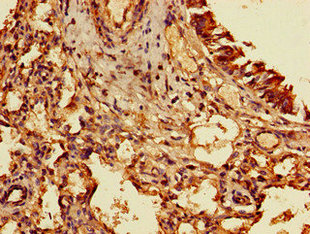

Immunohistochemistry of paraffin-embedded human pancreatic cancer using CSB-PA889078LA01HU at dilution of 1:100